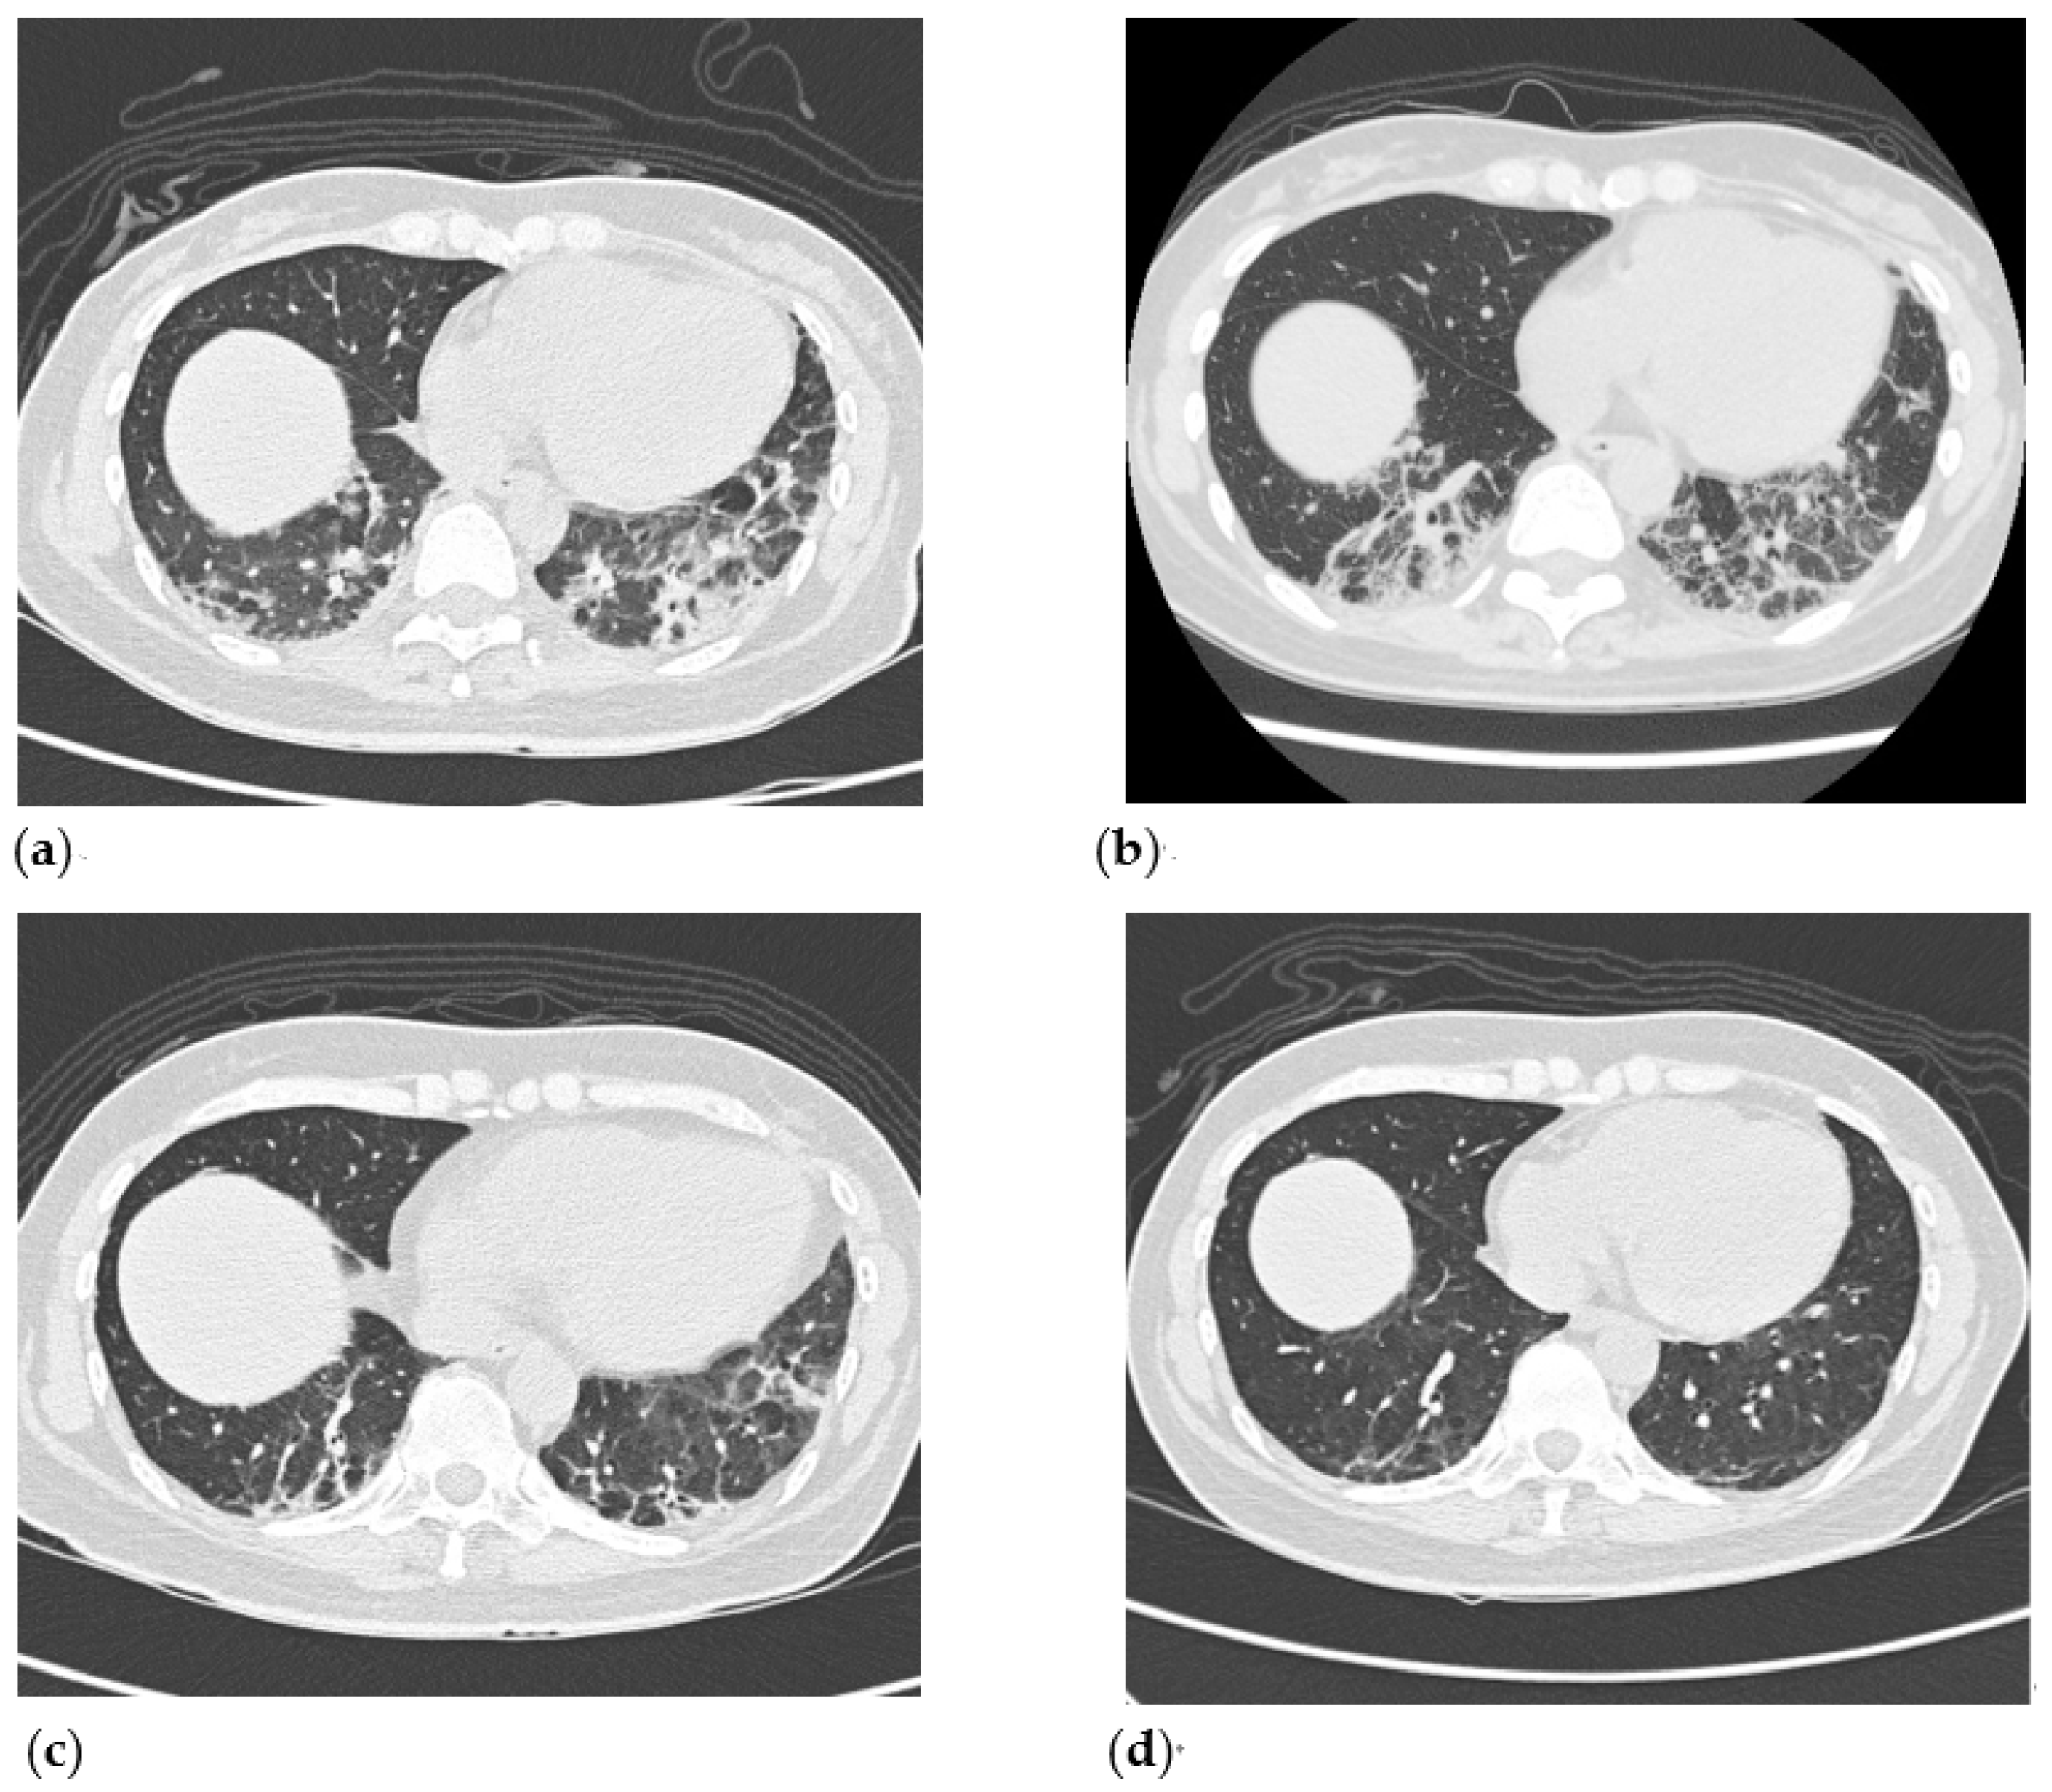

2. Case Presentation